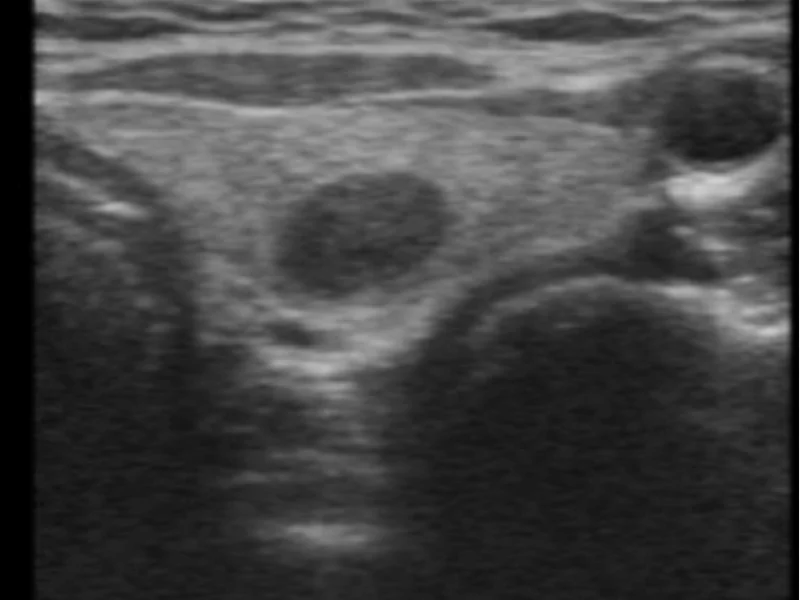

- Surgiram características novas no ultrassom (calcificações, fluxo interno)

Em nódulos menores que 2 cm, a PAAF pode não ser nem necessária, dependendo das características no ultrassom (classificação TI-RADS baixa). Quando indicada e bem feita, o resultado Bethesda II é confiável.